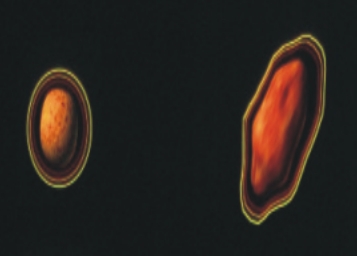

分析三度空間順形放射治療(光子刀),於腹腔及骨盆腔惡性腫瘤之治療成效。三度空間順行治療(3-D

conformal radiotherapy,3DCRT),源起於1996年之醫用三度空間放射治療計劃系統技術之利用,配合電腦斷層或核磁共振之影像取得,可將劑量輸出更接近腫瘤部位,可增加腫瘤的控制率並減少正常組織副作用之生物優勢。本中心於88年開始使用此技術,此篇報告以財團法人仁愛綜合醫院大里院區腫瘤治療科,治療的25例前列腺癌,17例肝內之肝細胞癌或膽道癌、15例後腹腔轉移癌及12例胰臟癌患者為分析主體。

所使用的治療方式是以三度空間的順形治療技術,即由電腦斷層或核磁共振影像,確定治療之標的物,且將影像輸入三度空間治療計劃系統,由此軟體之運算可決定最適合腫瘤形狀及大小之治療照野、治療角度及所需之治療附屬工具之使用機會,以幾近完美之劑量分佈涵蓋腫瘤所需治療之範圍。此外再搭配良好之體外固定系統(真空墊)以確定重覆治療之準確性。所有治療均可於門診實施。所使用腫瘤劑量為45~60葛雷(Gy),分次於5~6週進行(每天一次,每週五天)。